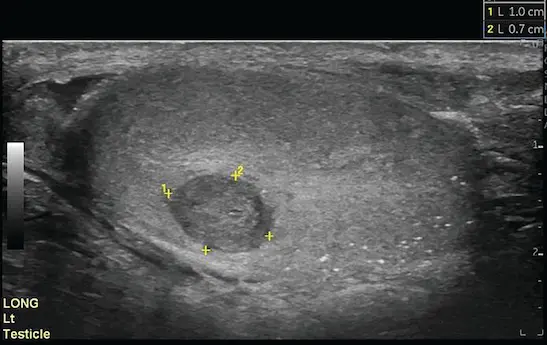

1. Ecografía Testicular (Ultrasonido)

Es la prueba principal. Nos permite ver dentro del escroto con ondas sonoras. Confirma si el bulto es sólido (sospechoso de cáncer) o simplemente está lleno de líquido (quiste o hidrocele inofensivo).